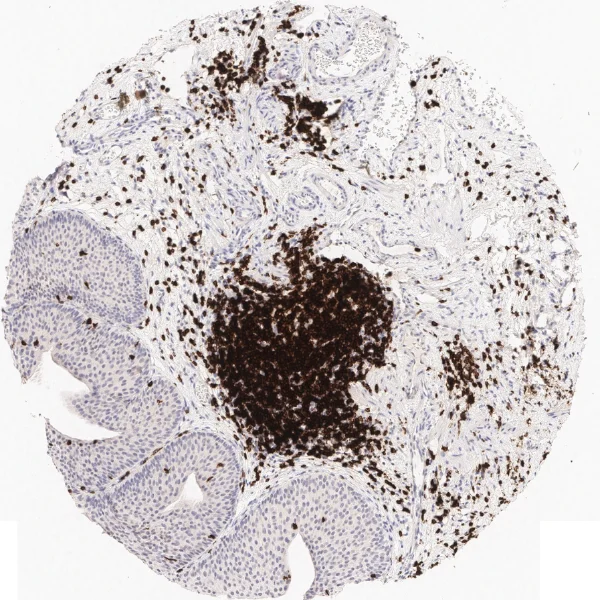

Another example on TMA analysis is our IHC Immune Status in situ APP. Here the task was to develop a streamlined workflow for tissue classification (epithelium, stroma, lymphoid cluster).

Marker positive cells (for CD3+) were identified and spatial analysis was peformed, which would allow for the calculation of how many and which types of cells are located in defined distances from the object of interest (epithelium or lymphoid cluster). In the below example the App was applied to Tissue Microarrays (TMA) of an inflamed bladder.

One of the most notable features of StrataQuest is the machine learning-based tissue classification. To train the algorithm, the user marks regions assigned to different tissues and trains the classifier on the sample; later this workflow can be used on other samples. The following images represent the outcome of the classifier: (g) epithelium is detected in blue; (h) displays the lymphocyte cluster in light blue. These algorithms (or masks) can be combined to achieve a better visualization: (i) epithelium is displayed in blue, lymphocyte cluster in light blue and stroma in yellow.

Beside the tissue classification itself, StrataQuest is capable of performing proximity analysis. It is possible to define specific proximity ranges; in the following case each range marked by different colors is 20µm. Nuclei detection was applied and CD3+ cells are shown in green, negative cells in yellow; (j) proximity ranges for the epithelium and (k) proximity ranges for the lymphocyte cluster.

Apart from visual image analysis, StrataQuest outputs quantitative numbers. This way, it is possible to acquire and validate much more information. For example, StrataQuest can show how many cells are detected in each range: through the establishment of gates, 5.06% of CD3+ cells were found to be very close (in 20 µm range) to the epithelium.